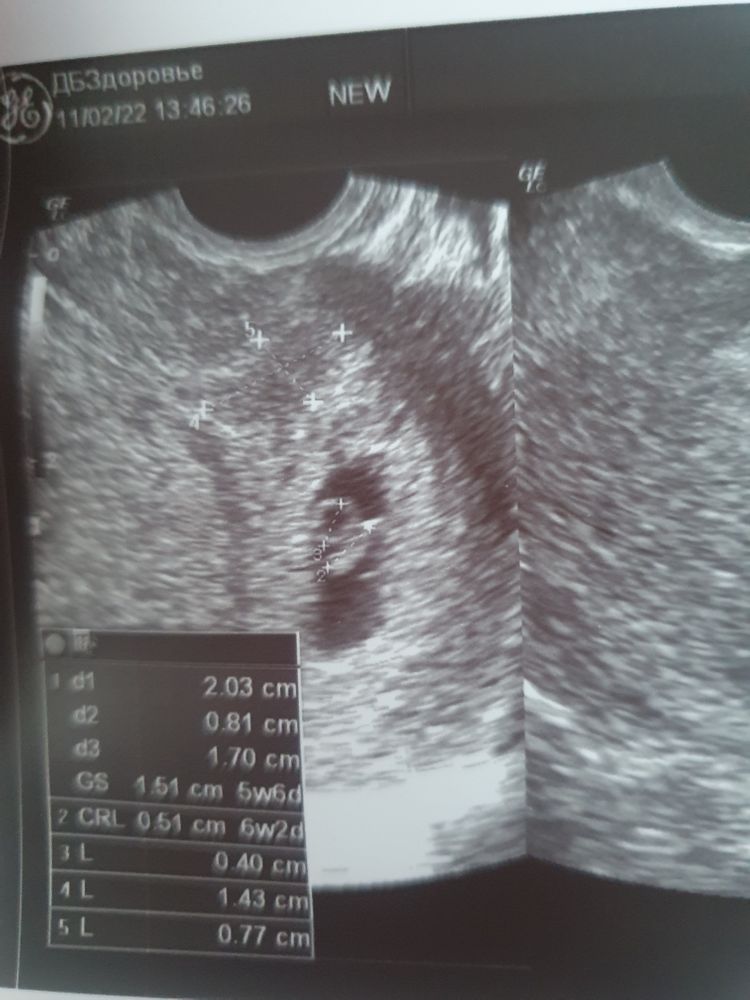

25дпп, кровит из-за гематомы. Узи. ❤ +

Всё о нашей беременностиВстала утром и снова здравствуйте. Снова алой крови капли. Сорвались поехали с мужем на узи. Нашли гематомку небольшую. Постельный режим наше все ..

Ктр 0.5см, жм 0.47см, пя 1.51см, ❤ +

Срок 6+2